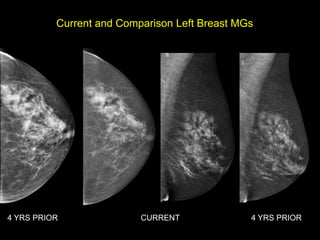

Current Bilateral Mammogram

RCC      LCC             RMLO       LMLO

Current and Comparison Left Breast MGs

4 YRS PRIOR               CURRENT              4 YRS PRIOR

HISTORY โ€ข 65 yofemale โ€ข Presents from OSH with worsening โ€žleft breast swellingโ€Ÿ for 8-9 months โ€ข New 1 month history of โ€žchange in left nippleโ€Ÿ

Current and ComparisonLeft Breast MGs 4 YRS PRIOR CURRENT 4 YRS PRIOR

US retroareolar region US Left upper outer breast

Grade 2 InvasiveLobular Carcinoma with LN positive for Metastatic Adenocarcinoma SURGERY โ€“ Mastectomy with LN dissection

Invasive Lobular Carcinoma โ€ข10-15% of all invasive breast ca โ€ข Sensitivity of MG 57-81% โ€“ Mass most common โ€“ usually spiculated (44- 65%) โ€“ Distortion 10-34% โ€“ Asymmetry 1-14% โ€ข Much less freq assoc with calcs than IDC โ€ข Sensitivity of US 68-98% โ€“ Spiculated mass โ€“ Shadowing Lopez et al. Radiographics 2009; 29:165.

Invasive Lobular Carcinoma โ€ขSensitivity of MRI up to 95% โ€“ Changes in clinical management up to 50% โ€“ Changes in surgical management up to 28% โ€ข Kinetics โ€“ progressive more typical than washout Lopez et al. Radiographics 2009; 29:165.